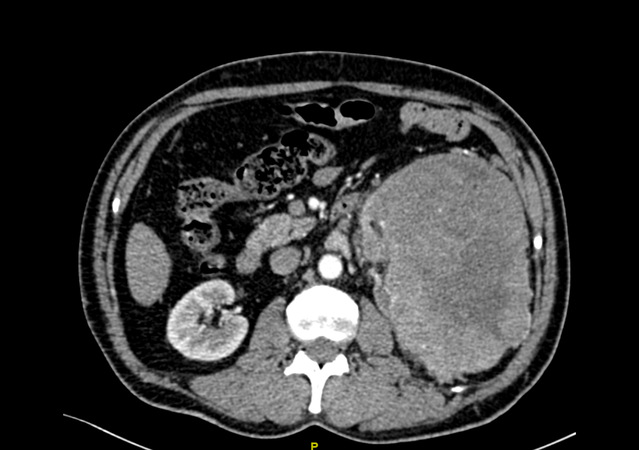

经过CT等检查,发现陈先生的左边肾脏上长了一个巨大的肿瘤,大小约16.6cm*11.1cm,也正是因为这个原因,导致了腰痛、血尿、排尿困难等一系列症状。

探花直播 泌尿外科团队仔细分析了患者的病情、症状以及影像学检查,发现陈先生体内的这一颗“定时炸弹”比既往所处理过的任何一例肾脏肿瘤都要庞大,而且已经充满了患者的后腹腔,更为棘手的问题在于肿瘤恶性可能极大,供养这颗肿瘤生长的血管,也密密麻麻的盘曲在肿瘤周围,给手术治疗带来了极大的困难。如果按照既往的治疗方案,对于如此巨大的肾脏肿瘤,而且同时合并肿瘤出血带来的粘连等一系列困难,往往选择开放手术,也就是老百姓口中的“开大刀”。但是众所周知,开放手术存在切口长、手术创伤大、术后恢复缓慢以及术后并发症多等诸多缺点。思虑再三,经过泌尿外科科内讨论后,最终决定给陈先生实行了腹腔镜下微创手术,减少手术带来的损害及痛苦。

4月7日,经过团队成员的共同努力,陈先生顺利进行了腹腔镜下的左肾及肿瘤切除术。为了更准确的评估病情以及减少复发转移的风险,术中还同时进行了淋巴结清扫术,术后标本称重达1600克。有赖于微创手术的优势,手术之后,陈先生恢复良好。手术后的病理结果证实:左肾肿瘤为肾嫌色细胞癌,淋巴结未见明显转移,通过手术,已将肿瘤完整的切除,而患者也将有一个比较好的预后。